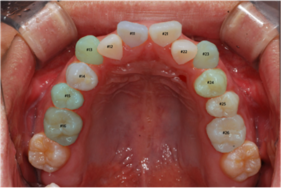

이미지/라벨링 예시

| 이미지 | 라벨링 | |

| upper |

치아 경계

| lower |

치아경계